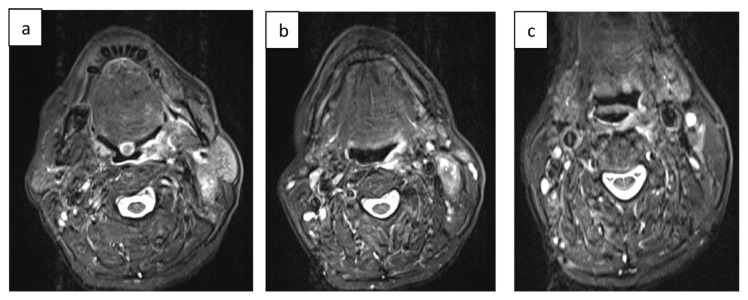

Abstract Image